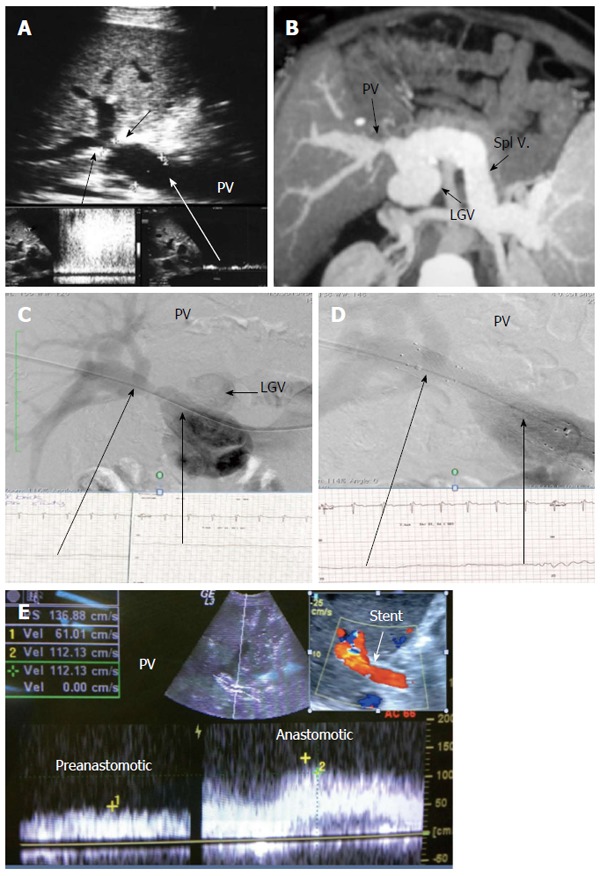

Post-operative developmental portal vein stenosis in a patient with attack of variceal bleeding, 1-year post-living donor liver transplantation. A: B-mode and pulsed Doppler image showing tight PV anastomotic stricture (arrows) and anastomotic jet (> 10-fold) compared to the pre-anastomotic velocity; B: MSCT angiography image demonstrating tight PV anastomotic stricture with aneurysmal dilatation of the left gastric vein; C: Percutaneous trans-hepatic portography demonstrating tight PV stricture and dilated left gastric vein, stealing the portal flow. The pressure gradient was 10 mmHg; D: Control portography after balloon dilatation and stent placement demonstrating wide anastomosis, normalization of the pressure gradient, improvement of the flow steal and disappearance of the left gastric vein filling; E: Color Doppler image after PV stent placement confirming improved portal flow with increased pre-anastomotic velocity and mild elevation of the anastomotic velocity. PV: Portal vein; LGV: Left gastric vein.

Figure 22.

Post-operative developmental portal vein stenosis in a 16-year-old boy with progressive splenomegaly and pancytopenia, 1-year post-left lobe living donor liver transplantation. A: Color US image showing PV anastomotic stricture and post-stenotic dilatation. The anastomotic velocity elevation was borderline (3-4-fold) compared to the pre-anastomotic velocity (not shown); B: Multi-slice CT angiography, reconstructed image, demonstrating moderate PV anastomotic stricture with post stenotic dilatation of the graft PV; C: Percutaneous trans-hepatic digital subtraction portography image, demonstrating moderate PV anastomotic stricture (> 50 %) with post-stenotic dilatation. The pressure gradient was 7 mmHg; D: X-ray image during balloon dilatation of the stricture. The pressure gradient was normalized and stent placement was not performed. PV: Portal vein; LPV: Left portal vein.

Figure 23.

Post-operative developmental portal vein stenosis 2-years post-living donor liver transplantation. B-mode and color US image demonstrating tight PV anastomotic stricture with color aliasing (arrows) and aneurysmal dilatation of the PV anterior segmental branch. PV: Portal vein.

In patients with clinical manifestations and radiological confirmation of significant stenosis, therapeutic intervention is mandatory. Interventional angioplasty and stent placement have become widely recognized as the first choice for treatment[80,81,89] (Figures 21 and 22).